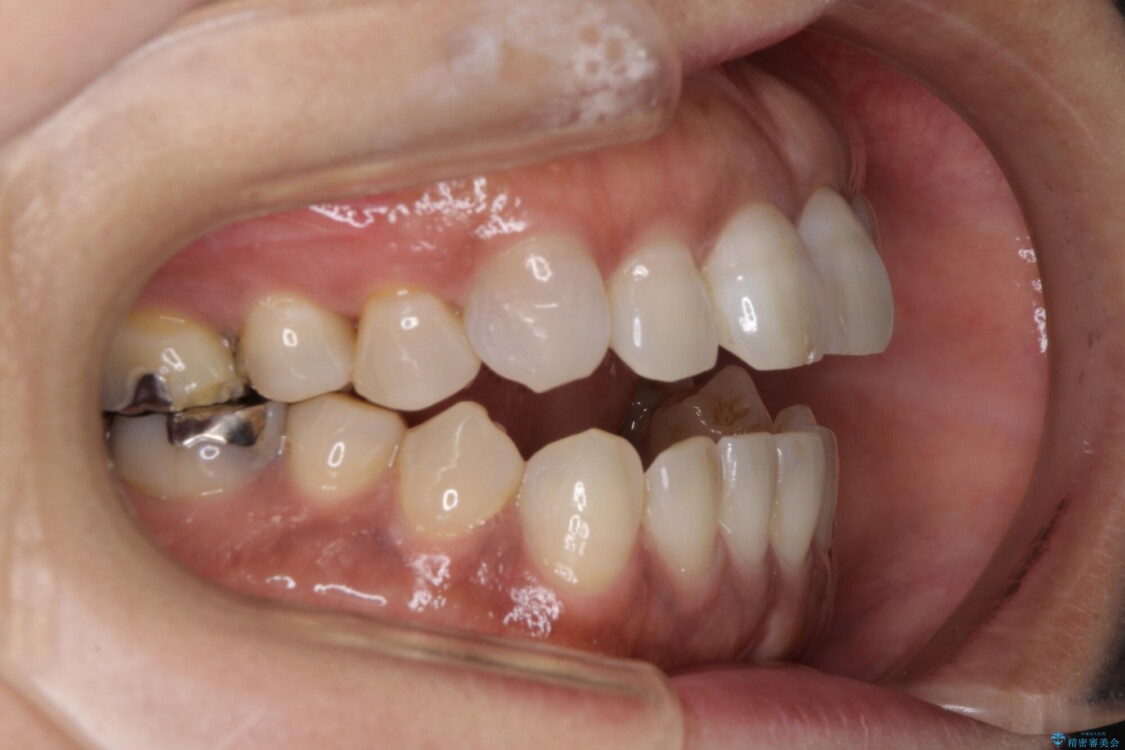

ほとんどの人が「開咬」と言うとき、それは前方の開咬を指します。前歯が開いている人は、上と下の前歯が外側に傾斜しているため、口を閉じたときに歯が接触しません。

開咬は不正咬合の一種で、顎を閉じたときに歯が正しく並んでいないことを意味します。

開咬の副作用は、審美的な問題から歯の骨折まで多岐にわたります。

- 美学。開咬の人は、歯が突き出ているように見えるため、歯の外観に不満を抱いている可能性があります。